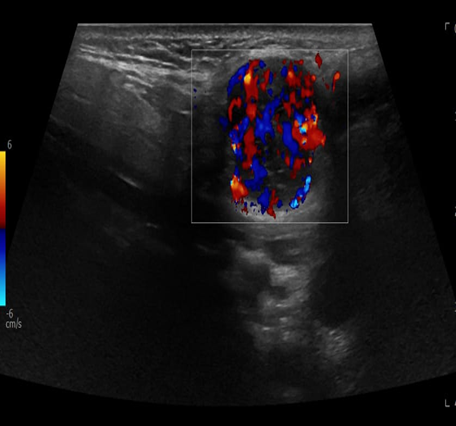

A 69-year-old male noticed a small painless lump in his left parotid region while shaving, Ultrasound examination of the area demonstrated a well-defined lesion measuring approximately 1.7x1.5 cm with internal vascularity, inseparable from the left parotid tail. The rest of the neck ultrasound was unremarkable; MRI was recommended to better define the lesion's origin before histopathological assessment. MRI revealed an oval-shaped, well-defined solid mass lesion in the left parotid gland, measuring about 2.2x1.9x1.3cm in maximum craniocaudally, transverse, and AP dimensions. The lesion is seen as separable from the deep part of the parotid gland, extending posteriorly, abutting the anterior aspect of the related sternomastoid muscle without definite muscle invasion. The lesion eliciting low signal in T1, heterogeneous low signal in T2 weighter images with heterogeneous post contrast enhancement. The main differential diagnoses considered were pleomorphic adenoma and Warthin tumor, although other possibilities could not be totally excluded. Surgical excision was performed. Histopathological analysis revealed Kaposi sarcoma within an intra-parotid lymph node. The lesion was excised with a margin of 0.5 cm. Although the findings were most consistent with a primary nodal Kaposi sarcoma, metastasis from other sites, particularly the skin, should be excluded (Table 1 and Figures 1-4).

Figure 2: Ultrasound with color Doppler for left parotid gland.